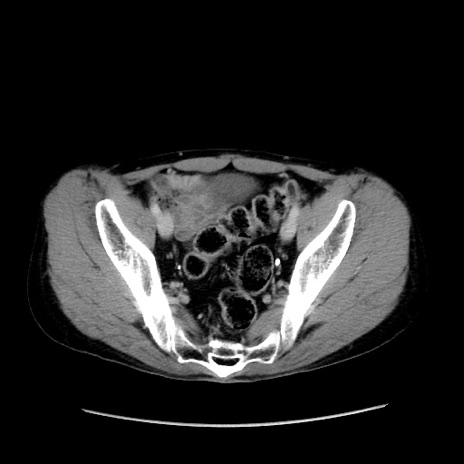

症例37(横断像)

【症例】40歳代 男性

【主訴】腹痛

【現病歴】4時間ほど前に電車に乗車中に臍部上より腹痛出現。徐々に増悪し起立困難となり、救急外来受診。生ものは数日食べていない。今朝お雑煮を食べた。

【身体所見】BT 36.8℃、BP 117/84mmHg、HR 91/min、SpO2 97%、苦悶様、腹部:臍上部広範囲圧痛あり、反跳痛±

【データ】WBC 8100、CRP 0.03